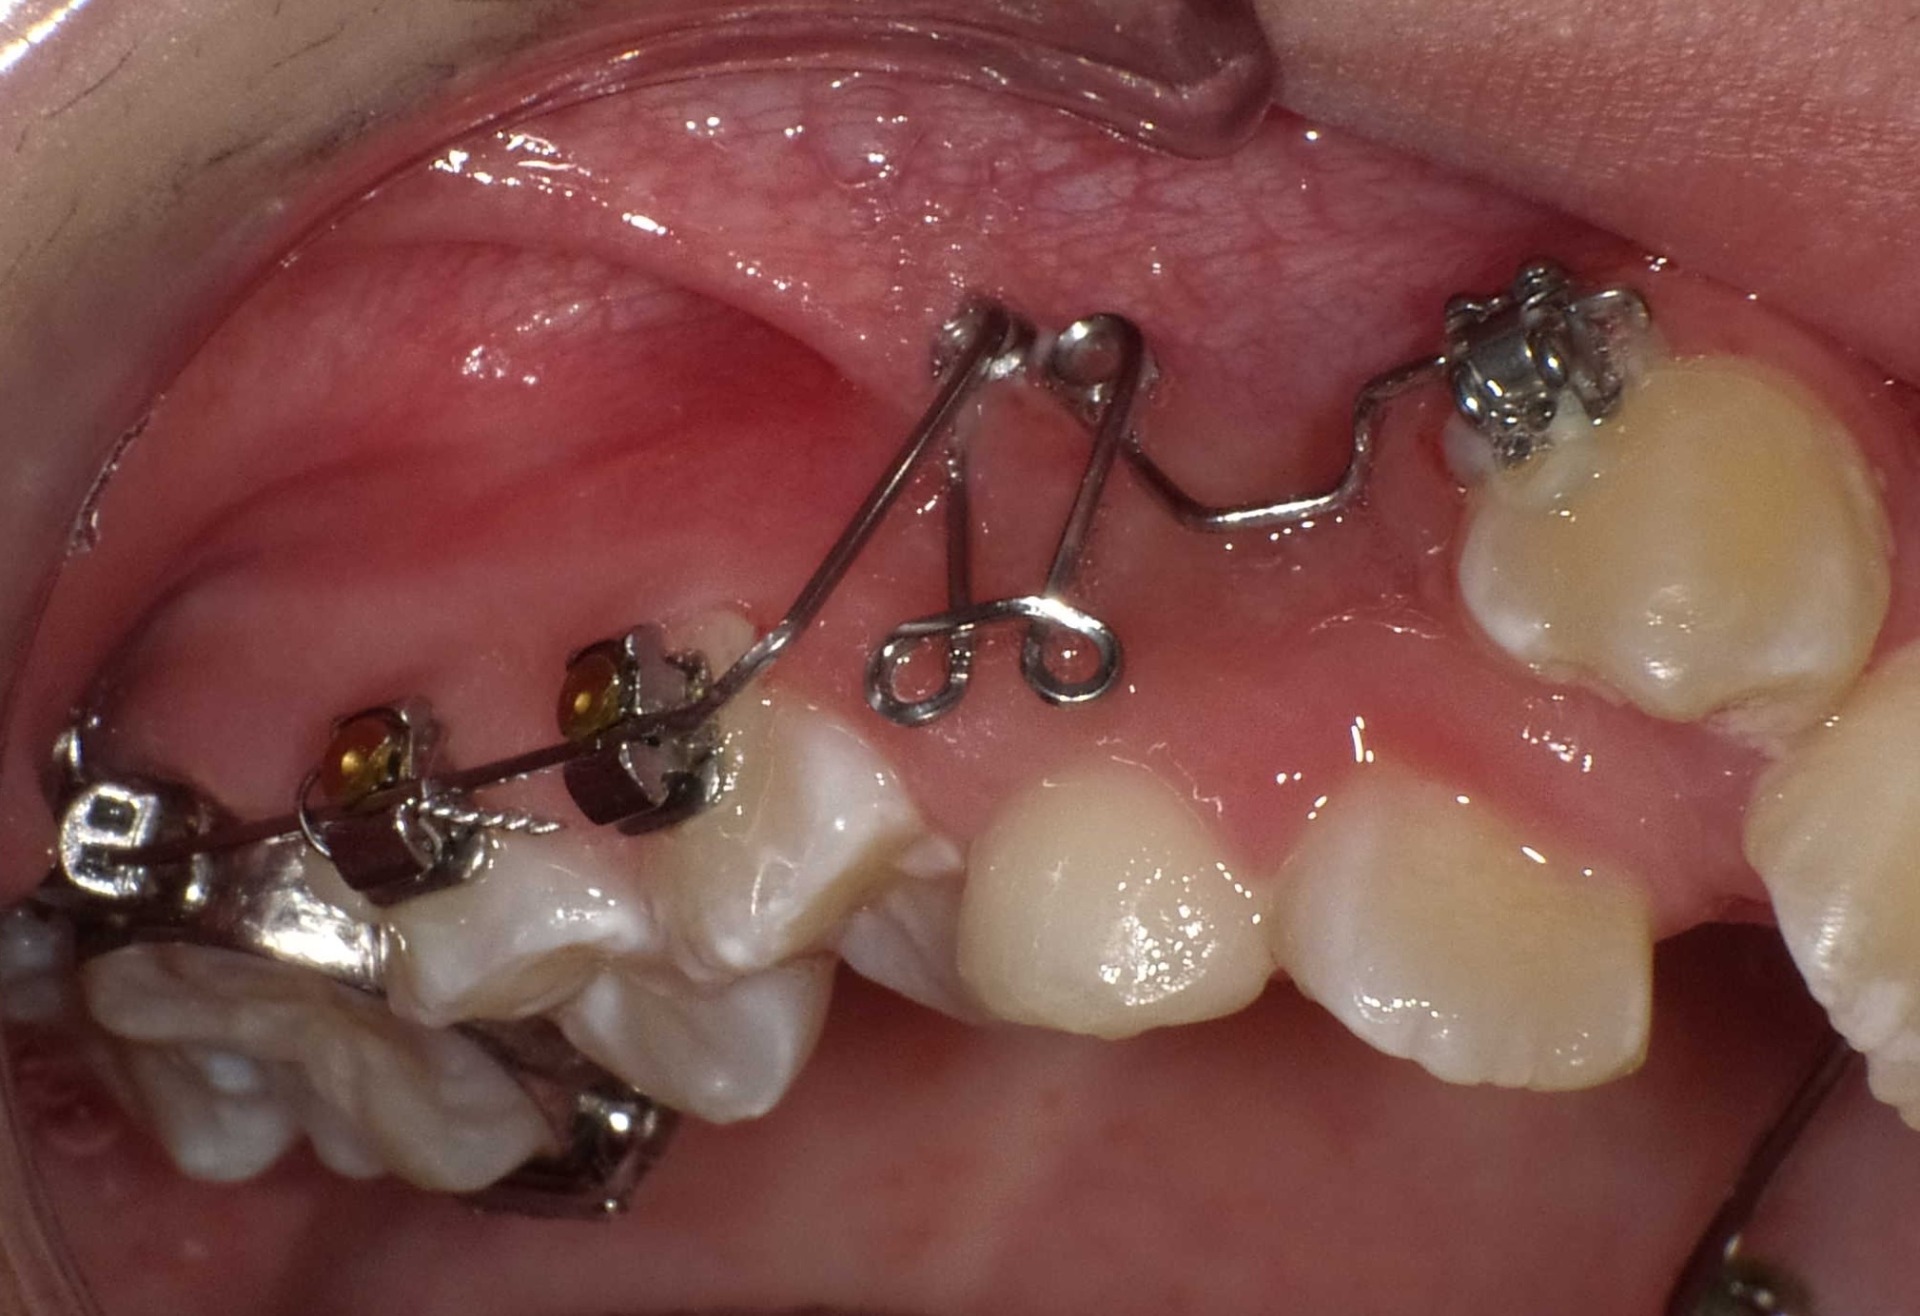

矯正前

| 症状 | 左上2番3番逆転症例 |

| 処置内容 | プレート拡大処置・マルチブラケット装置・クリアアライナー・ディスタライザー |